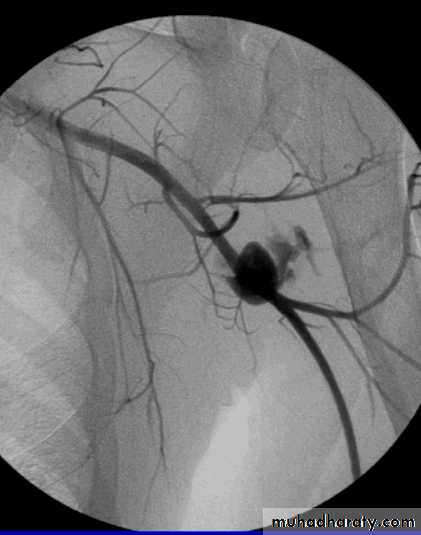

• At arteriography :, a narrow catheter is passed into the occluded vessel and left embedded within the clot.

• Tissue plasminogen activator (TPA) is infused through the catheter and regular arteriograms are carried out to check on the extent of lysis, which, in successful cases, is achieved within 24 hours.